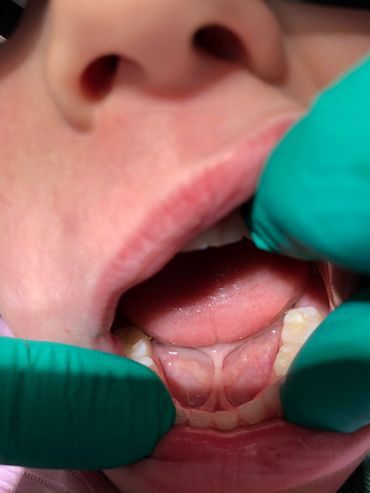

Whether you are struggling with an infant who is experiencing feeding issues, slow weight gain, reflux and/or colic symptoms. Or your older child who dealing with sleep concerns like snoring or grinding their teeth, speech impediments or a picky eater. Having a Functional Assessment early in life to screen for tethered oral tissues (tongue tie) can be life changing and prevent many bad habits associated with oral restrictions from forming. As an IBCLC & Orofacial Myologist, Sherrie has the experience and expertise to develop an indivualized care plan specific to your child’s needs.

Maybe your infant already had a release with another provider and is still struggling or no aftercare instructions were given. They may benefit from Oral Habilitation, contact Sherrie at info@sherriepruitt.com to see if this therapy could be beneficial to your little one.

Preparation is key, both mentally and physically and is just as important as the after care. This care is never one size fits all, Sherrie ensures pre and post operative care is tailored to fit each child’s individual needs. For some, more extensive therapy is required, inquire with Sherrie for pricing and scheduling of these therapies.